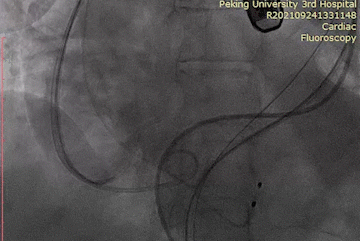

抓捕器左侧入路

圈套瓣膜